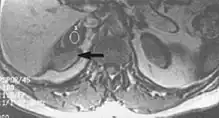

Flow can manifest as either an altered intravascular signal (flow enhancement or flow-related signal loss), or as flow-related artifacts (ghost images or spatial misregistration). Flow enhancement, also known as inflow effect, is caused by fully magnetised protons entering the imaged slice while the stationary protons have not fully regained their magnetization.[1] The fully magnetized protons yield a high signal in comparison with the rest of the surroundings. High velocity flow causes the protons entering the image to be removed from it by the time the 180-degree pulse is administered. The effect is that these protons do not contribute to the echo and are registered as a signal void or flow-related signal loss (Fig. 2).[1] Spatial misregistration manifests as displacement of an intravascular signal owing to position encoding of a voxel in the phase direction preceding frequency encoding by time TE/2.The intensity of the artifact is dependent on the signal intensity from the vessel, and is less apparent with increased TE.[1]